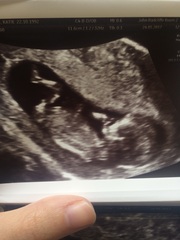

Bisquick I think pregnancy is a valid reason for getting a bit more 'involved' in things than usual. I think being nervous as well is round fair, it's the unknown, and this could have a huge impact on our children's future. Or it could not.